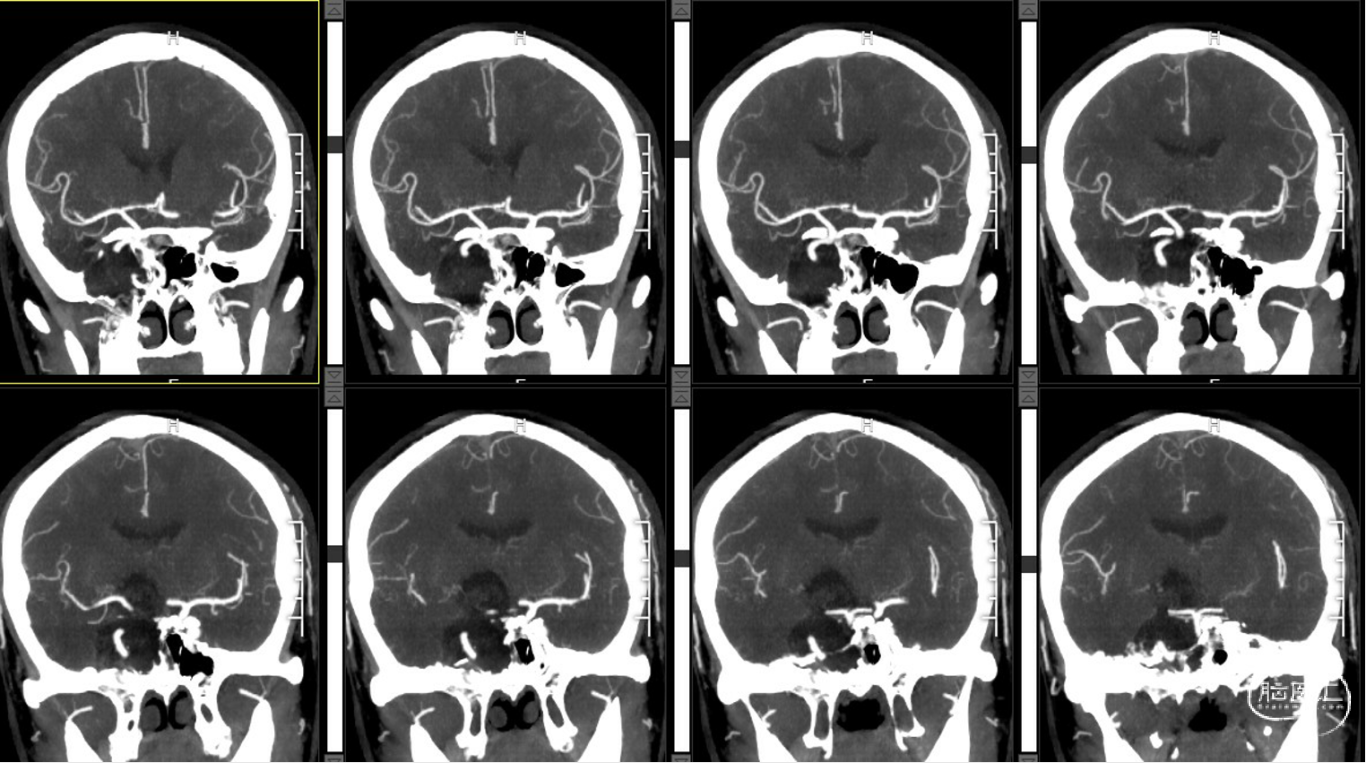

外院CT示:右侧颅底占位性病变,临近骨质部分吸收。

外院MR示:右侧颞底、桥小脑角区及鞍内占位,考虑表皮样囊肿伴破裂可能。